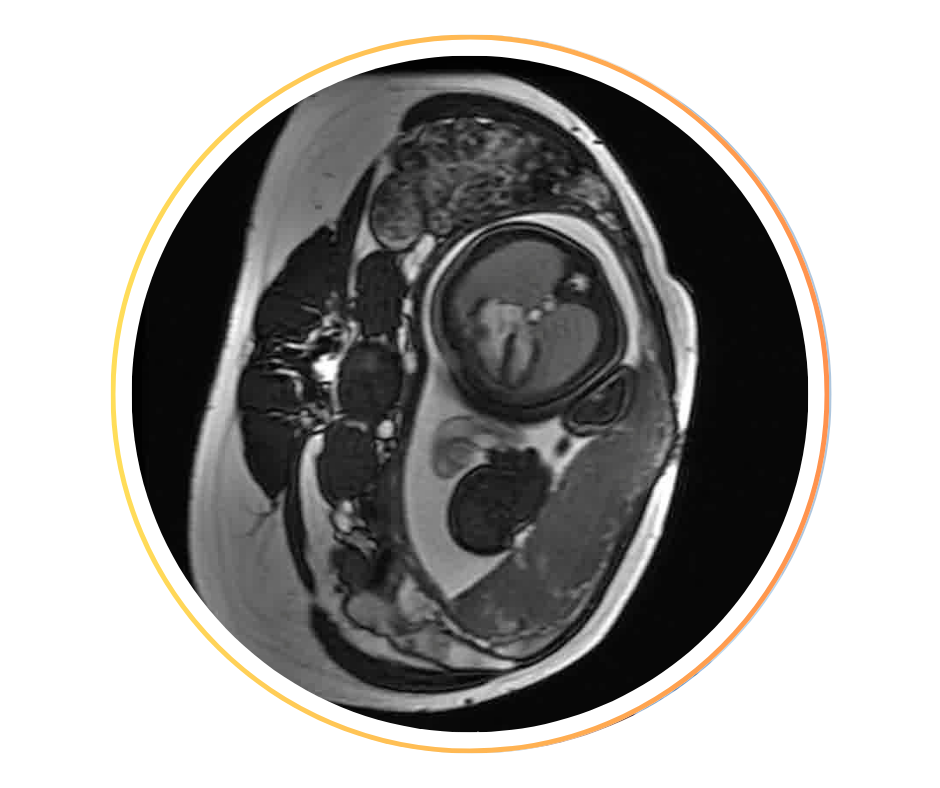

• Placenta, fonctionnement normal et pathologies placentaires : fonctionnalité placentaire normale et pathologique, imagerie multimodale (ASL, BOLD, T2*, DCE, …), placenta pathologiques (monochoriales, …).